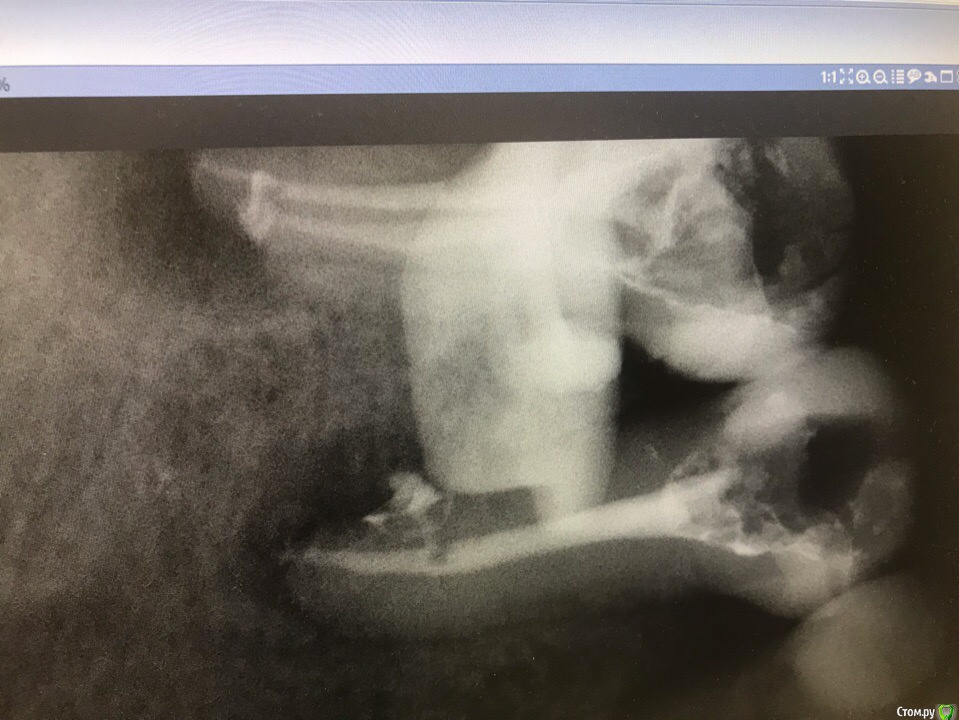

1586Doc Опубликовано 30 марта, 2019 Автор Поделиться Опубликовано 30 марта, 2019 (изменено) Еще немного работы45 зуб эндо и пломба и 46 зуб эндо и пломба на снимке справа Изменено 30 марта, 2019 пользователем 1586Doc Ссылка на комментарий